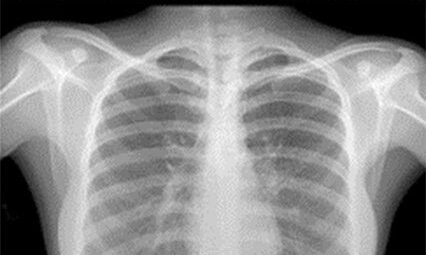

Medical X-rays produce highly detailed images of tissues and structures inside the body. If X-rays traveling through the body also pass through an X-ray detector on the other side of the patient, an image will be formed that represents the shadows formed by the objects inside the body.

Radiological density, a key concept in radiography, is a measure of a material’s resistance to the passage of X-rays. It is determined by both the density and the atomic number (the number of protons in an atom’s nucleus) of the materials being imaged. For example, structures such as bone contain calcium, which has a higher atomic number than most tissues. Because of this property, bones readily absorb X-rays and, thus, produce high contrast on the X-ray detector.

As a result, bony structures stand out distinctly, appearing whiter than other tissues against the black background of a radiograph. This stark contrast is a key feature of radiographs. Conversely, X-rays pass more readily through less radiographically dense tissues, such as fat and muscle, as well as through air-filled cavities, such as the lungs. These structures appear in shades of gray on a radiograph, creating a nuanced visual representation of the body’s internal structures.